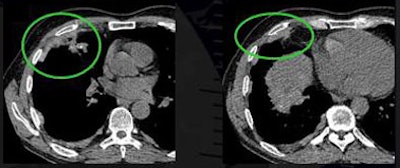

Conversely, 14% of plaques were lobulated, 2% were asymmetric with a right-sided dominance, and 1% were associated with pleural effusions. Eleven percent of patients had diffuse pleural thickening.

| Researchers found that more than 86% of pleural plaques were completely flat and 91% were symmetrical. Eleven percent of patients had diffuse pleural thickening (top). Plaques that were asymmetrical in shape and mass-like were considered suspicious for malignancy (above). Plaques were detected in the lung fissures, mediastinum, diaphragm, and costal regions (below). All images courtesy of Dr. Heidi Roberts. |